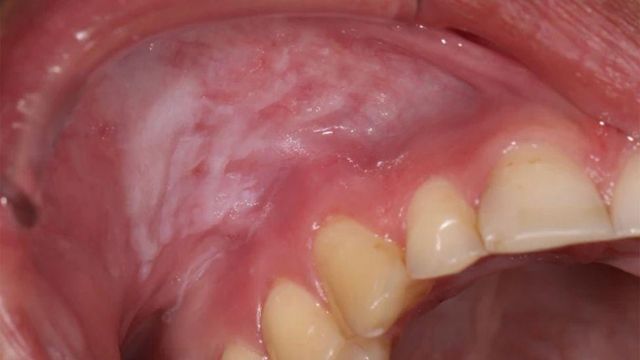

파우치가 잇몸에 미치는 손상에 대한 우려 또한 점점 커지고 있다.

니코틴 파우치를 1년 넘게 사용해 온 핀은 결국 "입 안이 완전히 너덜너덜"해졌으며, 한 번은 "잇몸의 절반이 벗겨졌다"고 말했다.

영국 본머스에 있는 스웨덴 출신 치과의사 패트릭 사라비 박사는, 파우치를 사용하는 환자들 중 일부가 치아 뿌리가 보일 정도로 깊은 잇몸 병변을 겪는 사례를 치료해 오고 있다.

그는 "니코틴 파우치가 장기적으로 끼치는 손상은 정말 심각한 우려를 낳고 있다"고 말했다.

니코틴 파우치에 대해 2년간 연구를 해 온 사라비 박사는 이 제품이 국소성 치주질환과 국소성 골손실 위험을 높인다고 설명했다.

16~29세의 25%가 이 제품을 사용하고 있는 스웨덴에서 치과 의사들은 점점 더 많은 환자들이 심한 염증을 겪고 있으며, 이 염증은 수개월에서 길게는 수년에 걸쳐야 낫는 경우도 있다고 말한다.